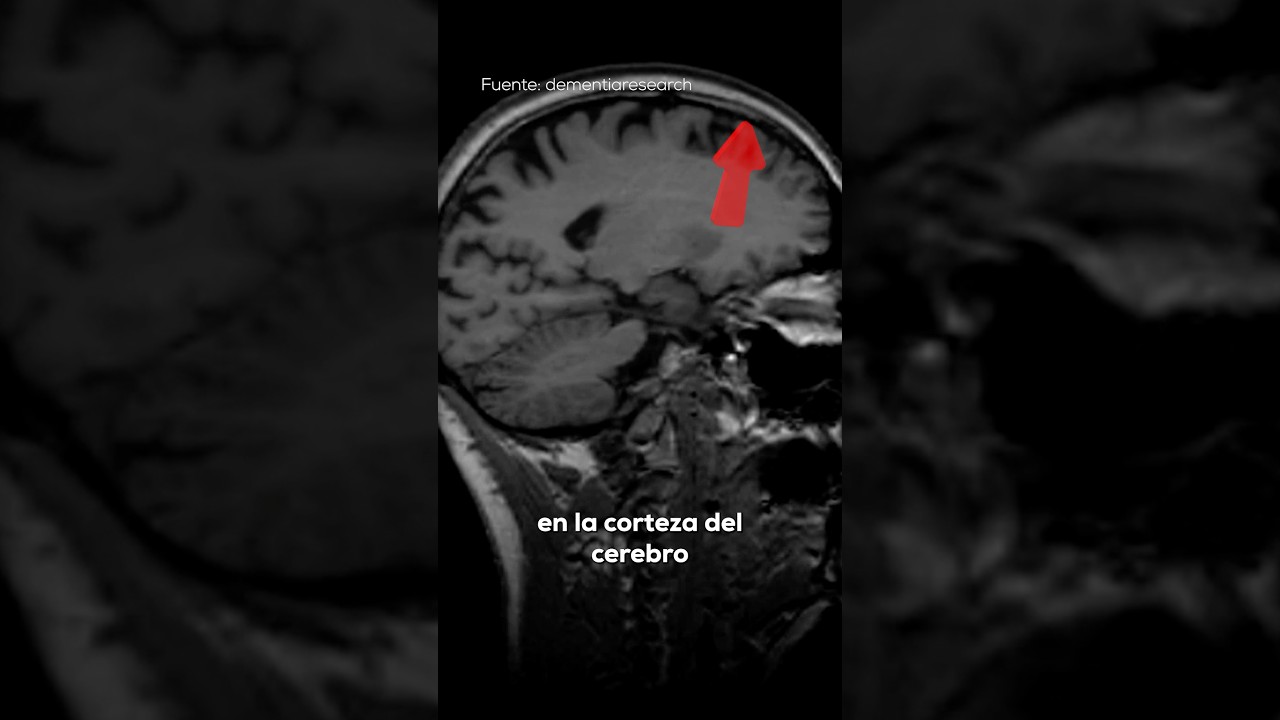

Cuando el cerebro comienza a atrofiarse, las áreas afectadas pueden perder su eficiencia. Por ejemplo, la atrofia en el hipocampo, una zona clave para la memoria, puede dificultar el aprendizaje y el recuerdo. En otros casos, la atrofia en la corteza motora puede afectar el control del movimiento.

Pruebas de imagen cerebral

Las técnicas de neuroimagen son esenciales para confirmar la atrofia cerebral. Entre las más utilizadas están:

- Resonancia magnética (RM): permite visualizar con detalle la estructura cerebral y medir la pérdida de volumen.

- Tomografía computarizada (TC): útil para detectar cambios en el tamaño cerebral y lesiones.

Estas imágenes ayudan a identificar áreas específicas afectadas y a diferenciar entre atrofia normal y patológica.